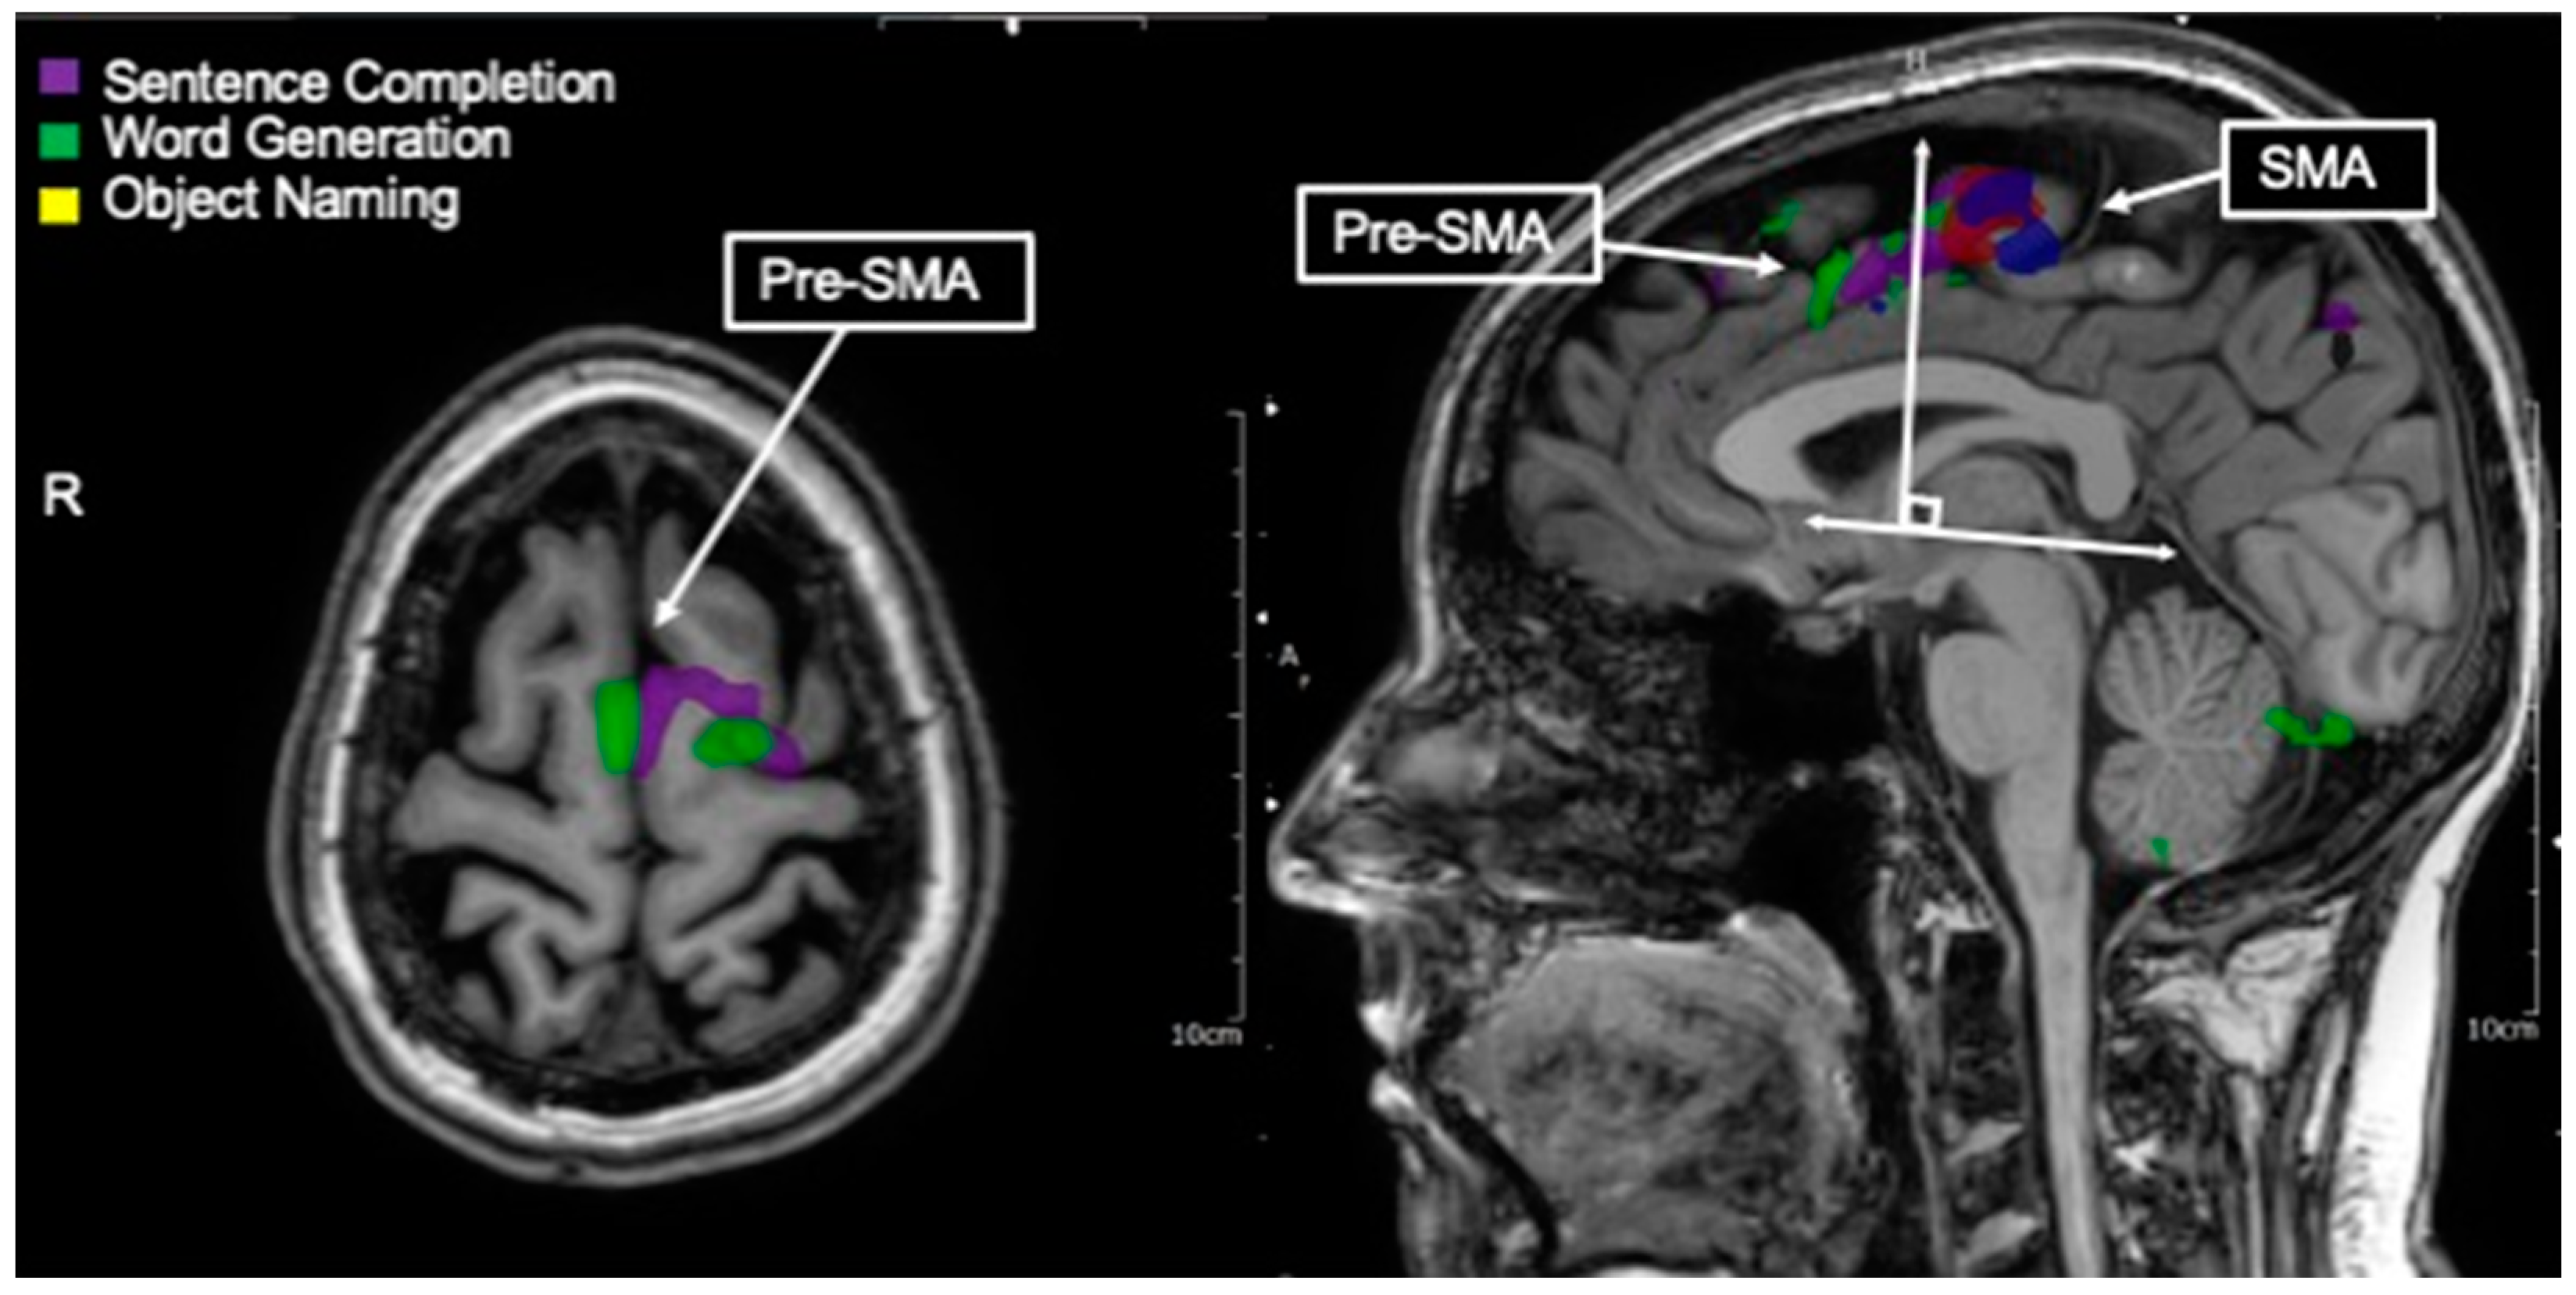

3.9. Pre-SMA/Language SMA